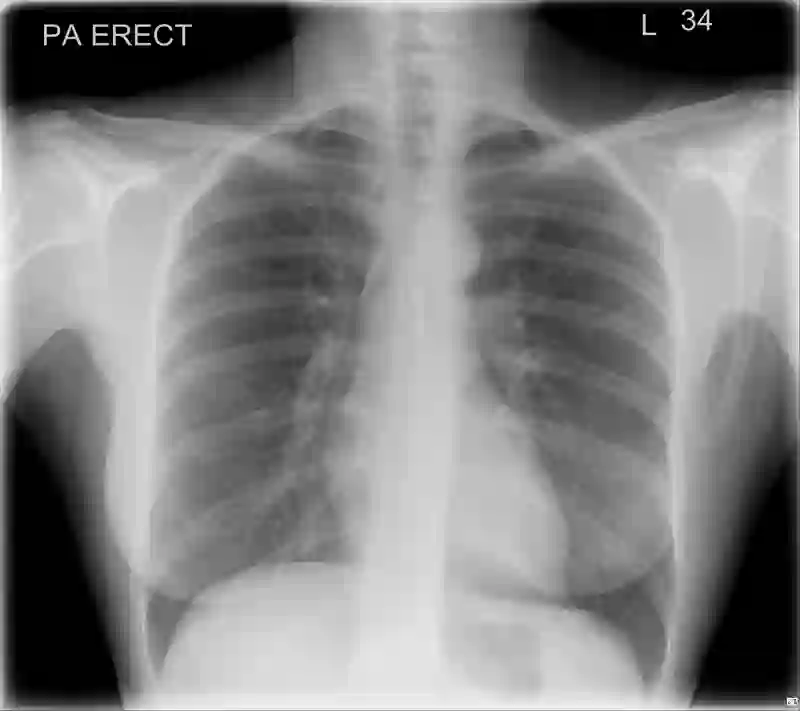

Chest radiography has been a recommended procedure for patient triaging and resource management in intensive care units (ICUs) throughout the COVID-19 pandemic. The machine learning efforts to augment this workflow have been long challenged due to deficiencies in reporting, model evaluation, and failure mode analysis. To address some of those shortcomings, we model radiological features with a human-interpretable class hierarchy that aligns with the radiological decision process. Also, we propose the use of a data-driven error analysis methodology to uncover the blind spots of our model, providing further transparency on its clinical utility. For example, our experiments show that model failures highly correlate with ICU imaging conditions and with the inherent difficulty in distinguishing certain types of radiological features. Also, our hierarchical interpretation and analysis facilitates the comparison with respect to radiologists' findings and inter-variability, which in return helps us to better assess the clinical applicability of models.